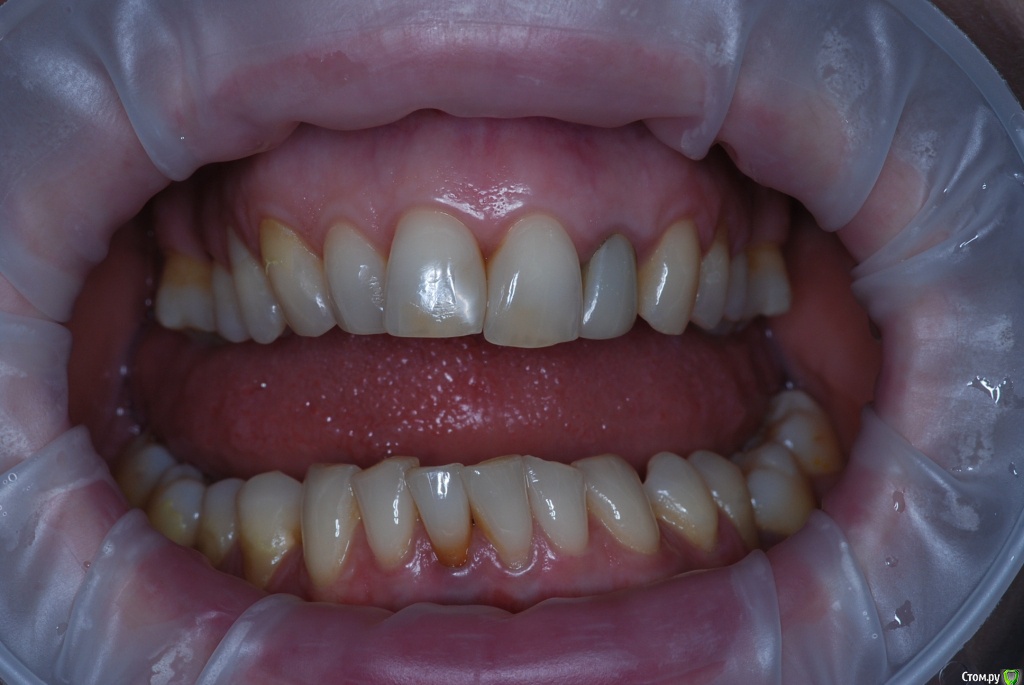

VVQW Опубликовано 6 декабря, 2016 Поделиться Опубликовано 6 декабря, 2016 В результате некачественной ортодонтии более 10 лет назад имеется такая картина. Посоветуйте что-можно сделать?Верхние 6-ки удалены перед брекет системой, по решению ортодонта. Верхние 8-ки не выросли, нижние 6-ки - удалены в подростковом возрасте до 14 лет. http://s019.radikal.ru/i639/1612/56/1345f17db908.jpg http://s019.radikal.ru/i630/1612/55/145ef7c813b2.jpg http://s017.radikal.ru/i440/1612/c2/74bd4da2643e.jpg http://s008.radikal.ru/i303/1612/b4/e80683ed7d2b.jpg http://s010.radikal.ru/i314/1612/74/6d2f9671b0d5.jpg http://s018.radikal.ru/i502/1612/97/9a15fcf4ddd3.jpg http://s020.radikal.ru/i715/1612/59/9bb4a006621f.jpg Ссылка на комментарий

VVQW Опубликовано 6 декабря, 2016 Автор Поделиться Опубликовано 6 декабря, 2016 Добрый день. Беспокоят клиновидки и их прогрессирование из-за неправильной окклюзии.Которая из-за неккоректно проведенного ортодонтическлго лечения. Одно из мнений ортодонтов, 50/50, что надо провести повторное лечение и восстановить зубной ряд имплантами. Вот только дальше варианты у всех свои. Если в верху подвинуть 7 к 5, есть место для импланта? Кость позволит? И наоборот если сделать место под 6, можно ли туда импоант поставить? Спасибо. Ссылка на комментарий